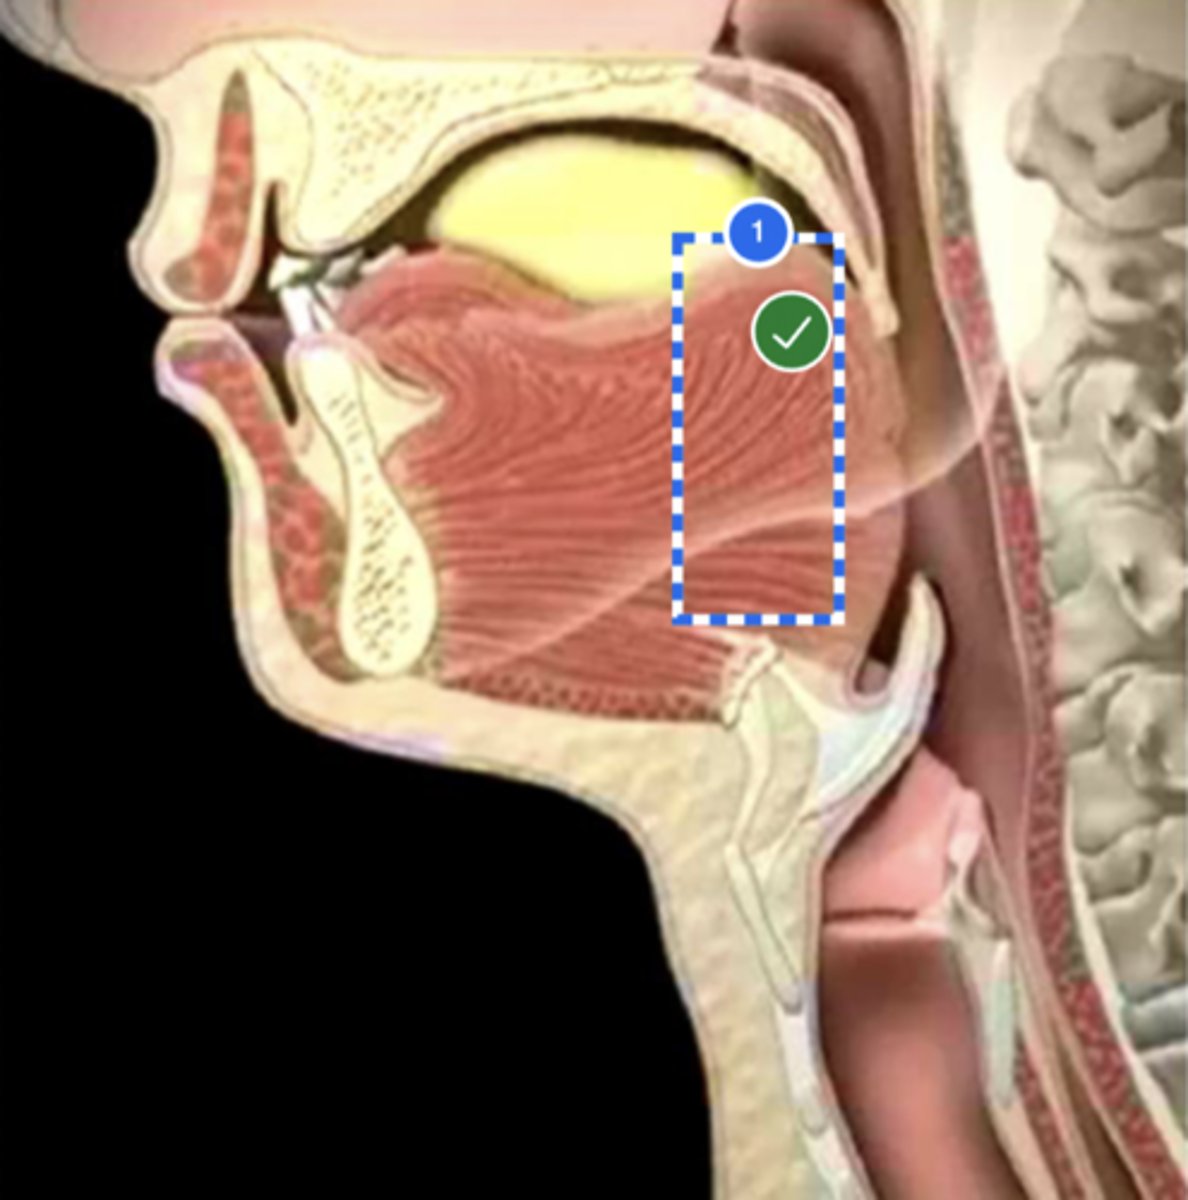

Label base of tongue (lateral view)

label anterior tongue (lateral view)

Label posterior/ back of tongue (lateral view)

Label Mandible (lateral view)

Label velum/ soft palate (lateral view)

Label hyoid bone (lateral view)

Label epiglottis (lateral view)

Label thyroid cartilage (lateral view)

Label posterior cricoid (lateral view)

Label trachea (lateral view)

Label upper esophageal sphincter (lateral view)

Label esophagus (lateral view)

Label posterior pharyngeal wall (lateral view)